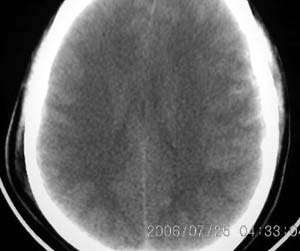

以下是引用lushijun在2006-7-25 21:02:00的发言:[br]1、双侧枕叶脑挫裂伤 2、硬膜下血肿 3、蛛网膜下腔出血[br]

以下是引用同在2006-7-25 21:11:00的发言:[br]双侧枕叶脑挫裂伤 硬膜下血肿 蛛网膜下腔出血

以下是引用kbzyycm在2006-7-25 22:54:00的发言:[br]1、双侧枕叶脑挫裂伤 、硬膜下血肿 蛛网膜下腔出血.[br]